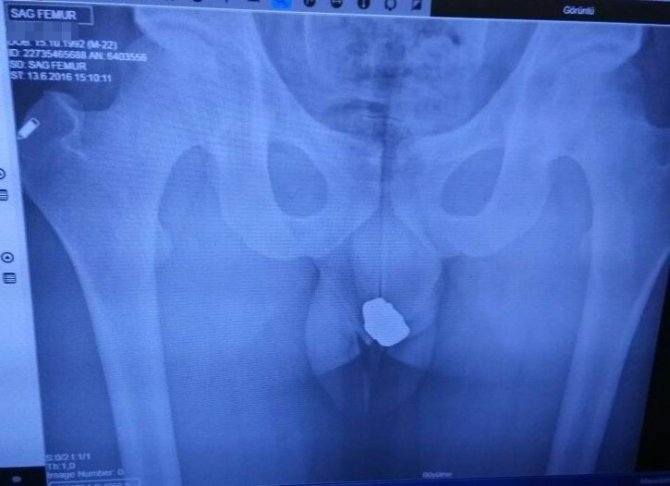

Otomobil İlçe Emniyet Müdürlüğü’nde parka çekilirken araçta yapılan aramada adreslerden çalınan cep telefonu ve gözlük de bulundu. Emniyet Müdürlüğü’ndeki sorgusunun ardından sağlık kontrolü için Beyşehir Devlet Hastanesi’ne götürülen Ö.A.’nın (24) yürüyüşündeki aksamadan şüphe eden polis ekipleri hastanede şahsın röntgen filmini de çektirdi. Çekilen röntgen filmi sonucu, şüphelinin adreslerden çalınan 3 altın yüzük, 4 adet küpe ve 2 adet yonca şeklindeki küçük altın kolyeyi makatında sakladığı ortaya çıktı.

Şüphelinin yüzük, kolye ve küpeleri bir naylon içerisine koyduktan sonra çakmak ateşiyle vakumlayarak makatına yerleştirdiği belirlendi. Röntgen filmi sonucunda, “Bu nedir’ sorusu sorulan şüphelinin, “küçükken yuttuğum taş” diye cevap verdiği, arama yapılacağının söylenmesi üzerine kendiliğinden çıkararak polise verdiği öğrenildi.